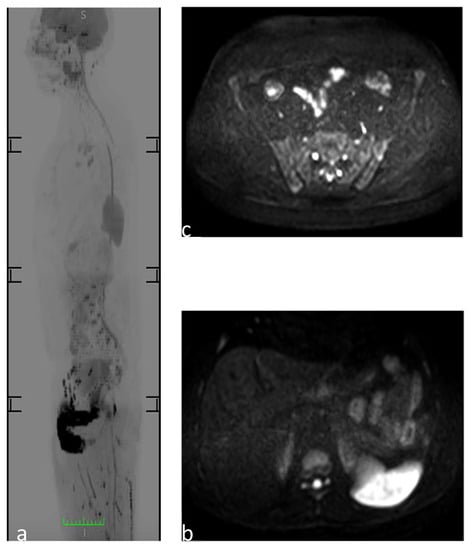

3.9. Avascular Multifocal Osteonecrosis (AVN)

3.10. Polyostotic Fibrous Dysplasia (PFD)

| AVN | Epiphysis long bones | Joints of the knees, shoulders, ankles, wrist, hips, and jaw | Ischemic lesions | |

| Hereditary ostechondromatosis | Flat bones or metaphysis of the long bones | NA | Multiple benign ostechondromas; signs of malignant transformation: growth of lesions after puberty or thickening of the cartilage hood | |

| PFD | There is no preferential bone location | NA | Multifocal benign proliferation of bone-fibrous tissue inside the bone marrow space | |